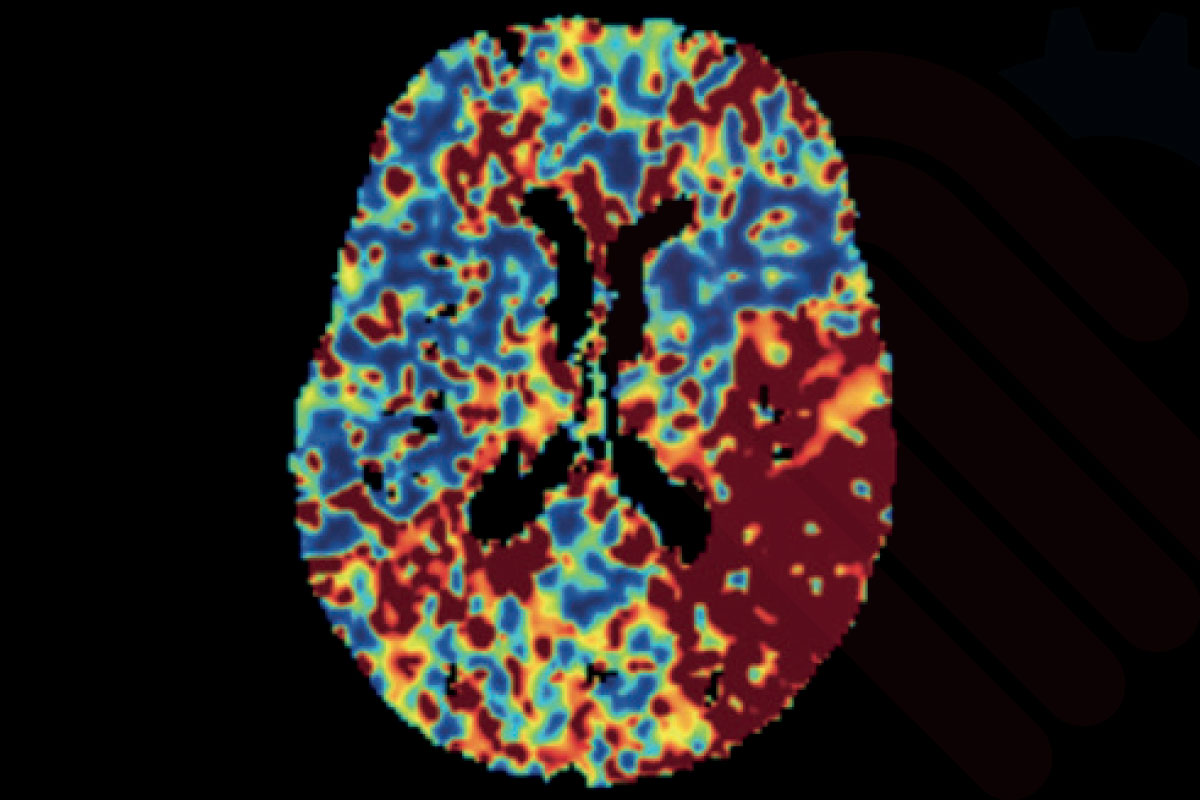

SVD tabanlı perfüzyon haritaları (CBF, CBV, MTT, Tmax)

Cercare Medical Neurosuite Stroke yazılımı, CT ve MR perfüzyon verilerini kullanarak SVD (Singular Value Decomposition) tabanlı analiz gerçekleştirir. Bu yöntemle beyin kan akımı (CBF), beyin kan hacmi (CBV), ortalama geçiş zamanı (MTT), zaman-gecikmesi (Tmax), maksimum yoğunluk projeksiyonu (MaxIP) ve tepe zamanı (TTP) parametreleri güvenilir biçimde hesaplanır.

Bu parametreler, iskemik inme vakalarında penumbra (kurtarılabilir doku) ile çekirdek infarkt (geri dönüşsüz doku) ayrımını netleştirmede kritik rol oynar. Özellikle Tmax > 6 sn ve düşük CBF değerlerinin birlikte değerlendirilmesi, infarkt çekirdeğini yüksek doğrulukla tanımlarken; CBV ve MTT haritaları penumbra bölgesinin belirlenmesinde önemli katkı sağlar*.

Klinik çalışmalar, bu analiz yaklaşımının hasta seçiminde doğruluğu artırdığını ve tedavi penceresinin uzatılmasına katkı sunduğunu göstermektedir*. Böylece hekimler, tromboliz veya trombektomi gibi tedavi seçeneklerini çok daha hızlı ve güvenilir biçimde planlayabilir.